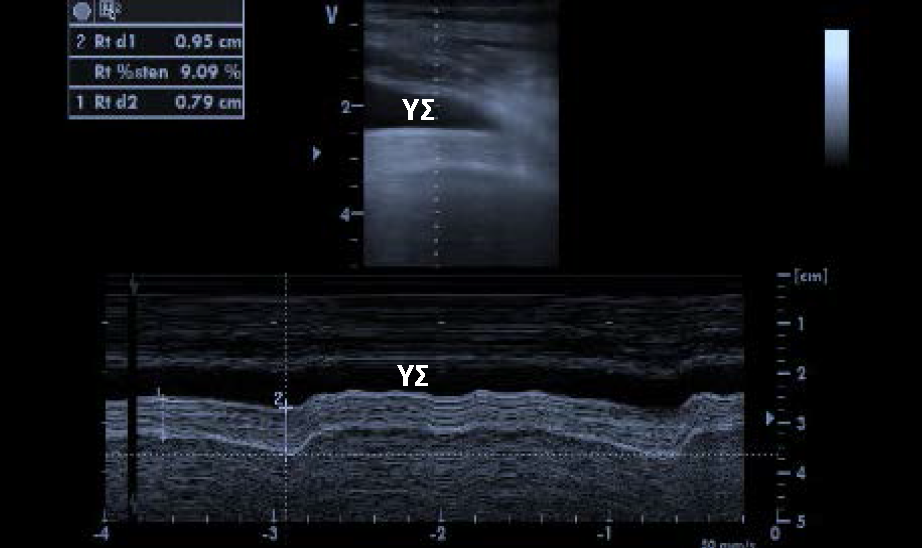

(βέλος). Κάτω κοίλη φλέβα Η

κάτω κοίλη φλέβα έχει μία διάμετρο που κυμαίνεται στα 20mm συμπίπτει κατά την εισπνοή ενώ διατείνεται κατά την

εκπνοή. (Εικ. 6). Με τη μέτρηση της μικρότερης και της μεγαλύτερης διαμέτρου

της κάτω κοίλης μπορεί να υπολογιστεί ο βαθμός της σύμπτωσης.[15] Στους

ασθενείς υπό μηχανικό αερισμό ο δείκτης σύμπτωσης δεν είναι τόσο αξιόπιστος

λόγω, αύξησης των ενδοθωρακικών πιέσεων. Μελέτες έχουν δείξει ότι η μέτρηση της

κάτω κοίλης φλέβας με χρήση υπερήχου έχει καλή συσχέτιση με την μέτρηση της

κεντρικής φλεβικής πίεσης μέσω κεντρικού φλεβικού καθετήρα. Η συσχέτιση αυτή

ωστόσο επηρεάζεται στους ασθενείς που υποβάλλονται σε μηχανικό αερισμό. Εικ. 6. Διάταση κάτω κοίλης φλέβας. Η μέτρηση διενεργείται 1 cm μετά την έκφυση της κοινής